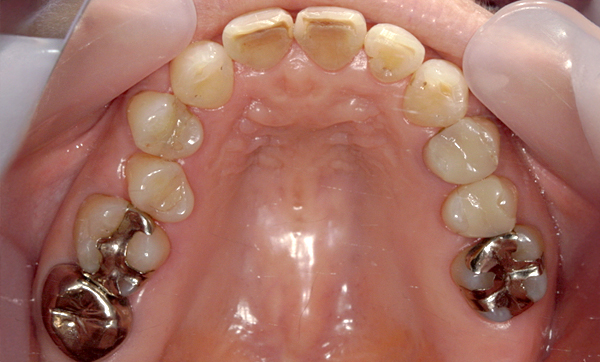

症例_012 上顎だけの部分矯正

治療期間:6ヶ月金額:24万円+税50代女性出っ歯八重歯上の前歯だけ